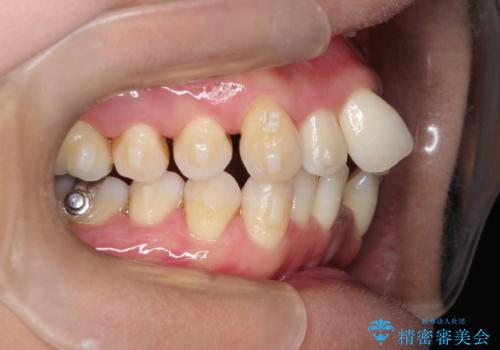

重度のガタガタのインビザラインによる非抜歯矯正

- 上下の歯のガタガタを主訴に来院されました。

インビザラインで奥歯を後方に移動させるのと、歯と歯の間をわずかに削ることでスペースを作り、歯を並べる計画としました。

しっかりとマウスピースを使用していただけたので、順調に治療を終えることができました。